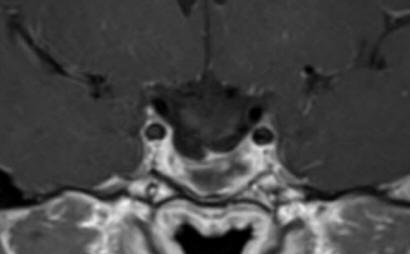

The patient was sent for thorough radio-ophthalmo-endocrine investigations. MRI of the sella with MRA done 16-December-2017 showed the tumor pushing the chiasm and optic nerves with suprasellar extension around 16.2 mm. The tumor has massive infrasellar extension reaching the naso-pharyngeal space abutting it. The tumor dimensions are 37.3x28.6 mm. There is no invasion of the cavernous sinuses. There is fluid level inside the tumor confirming the presence of apoplexy. Visual acuity of the right eye after correction 6/6. The left eye 6/0.05. There is massive scatoma left eye with less in the right eye. Prolactine 470 ng/ml, LH 1.19, testosterone 0.3. Considering the above data trans-sphenoidal approach with MRI control was advised. Mathematically speaking the volume of the tumor with the hypophysis is around 8.8 ml.

Fig:1- Follow up MRI performed 14-January-2019 3 months after completion of radiotherapy.